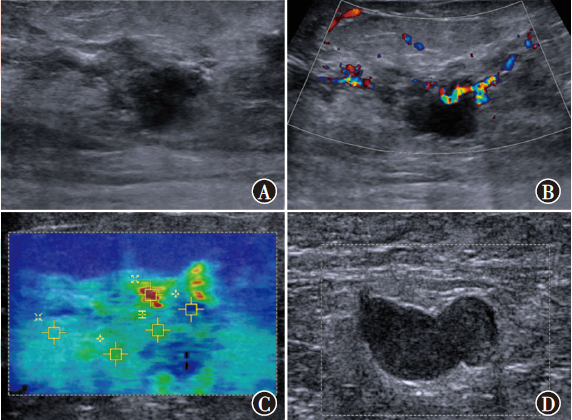

目的探讨常规超声联合剪切波弹性成像(SWE)鉴别诊断非肿块型导管原位癌(DCIS)和浸润性乳腺癌(IBC)的价值。方法选取2019年3月至2022年4月在南京大学医学院附属鼓楼医院收治的102例非肿块型乳腺癌患者作为研究对象,其中DCIS 32例、IBC 70例。比较非肿块型DCIS、IBC患者常规超声参数回声、微钙化、方位、后方回声、血流、腋窝淋巴结、乳腺影像报告与数据系统(BI-RADS)评分及SWE相关参数剪切波速度最大值(SWVmax)、剪切波速度最小值(SWVmin)、剪切波速度平均值(SWVmean)和剪切波速度中位数(SWVmedian),采用二元logistic回归分析鉴别诊断非肿块型DCIS和IBC的独立影响因素。根据多因素分析结果构建列线图预测模型,采用受试者操作特征(ROC)曲线评估预测模型的预测效能,采用校准曲线及决策曲线分析(DCA)评估模型的准确性和实用性。结果非肿块型DCIS、IBC患者间血流(χ2=8.47,P=0.004)、腋窝淋巴结(χ2=9.11,P=0.003)、SWVmaxZ=-3.32,P<0.001)、SWVmeant=3.00,P=0.003)、SWVmedianZ=-2.69,P=0.007)差异均有统计学意义。多因素分析显示,血流(OR=3.56,95%CI为1.28~9.89,P=0.015)、腋窝淋巴结(OR=3.04,95%CI为1.10~8.42,P=0.032)和SWVmaxOR=1.40,95%CI为1.13~1.73,P=0.002)均为鉴别诊断非肿块型DCIS和IBC的独立影响因素。基于血流、腋窝淋巴结、SWVmax构建列线图预测模型。ROC曲线分析显示,血流、腋窝淋巴结、SWVmax、预测模型鉴别诊断非肿块型DCIS和IBC的曲线下面积分别为0.64(95%CI为0.52~0.76)、0.66(95%CI为0.55~0.77)、0.71(95%CI为0.60~0.81)、0.79(95%CI为0.70~0.88),预测模型的鉴别诊断价值高于血流(Z=2.92,P=0.004)、腋窝淋巴结(Z=2.94,P=0.003)、SWVmaxZ=1.88,P=0.060)单独诊断。预测模型鉴别诊断非肿块型DCIS和IBC的C-index为0.77,校准曲线显示模型的预测概率接近实际概率。DCA表明,该模型能提供较高的临床净获益,具有一定的临床实用性。结论常规超声参数中的血流、腋窝淋巴结和SWE相关参数的SWVmax均为鉴别诊断非肿块型DCIS和IBC的独立影响因素,以此构建的列线图预测模型对非肿块型DCIS和IBC具有较高的鉴别诊断价值。

ObjectiveTo investigate the value of conventional ultrasound combined with shear wave elastography (SWE) in the differential diagnosis of non-mass ductal carcinomain situ(DCIS) and invasive breast cancer (IBC).MethodsA total of 102 patients with non-mass breast cancer admitted to Nanjing Drum Tower Hospital, Affiliated Hospital of Nanjing University Medical School from March 2019 to April 2022 were selected as the study objects, including 32 cases of DCIS and 70 cases of IBC. Conventional ultrasound parameters echo, microcalcification, location, posterior echo, blood flow, axillary lymph node, breast imaging reporting and data system (BI-RADS) score and SWE-related parameters maximum shear wave velocity (SWVmax), minimum shear wave velocity (SWVmin), mean shear wave velocity (SWVmean) and median shear wave velocity (SWVmedian) were compared between patients with non-mass DCIS and IBC. Binary logistic regression was used to analyze the independent factors for the differential diagnosis of non-mass DCIS and IBC. Based on the results of multivariate analysis, a nomogram prediction model was constructed and the predictive efficacy of the prediction model was evaluated by receiver operator characteristic (ROC) curve. Calibration curve and decision curve analysis (DCA) were used to evaluate the accuracy and practicability of the model.ResultsThere were statistically significant differences in blood flow (χ2=8.47,P=0.004), axillary lymph nodes (χ2=9.11,P=0.003), SWVmaxZ=-3.32,P<0.001), SWVmeant=3.00,P=0.003), SWVmedianZ=-2.69,P=0.007) between patients with non-mass DCIS and IBC. Multivariate analysis showed that, blood flow (OR=3.56, 95%CI: 1.28-9.89,P=0.015), axillary lymph nodes (OR=3.04, 95%CI: 1.10-8.42,P=0.032) and SWVmaxOR=1.40, 95%CI: 1.13-1.73,P=0.002) were independent factors for distinguishing non-mass DCIS from IBC. A nomogram prediction model was constructed based on blood flow, axillary lymph nodes and SWVmax. ROC curve analysis showed that, the area under the curve of blood flow, axillary lymph nodes, SWVmax, and prediction model for differential diagnosis of non-mass DCIS and IBC were 0.64 (95%CI: 0.52-0.76), 0.66 (95%CI: 0.55-0.77), 0.71 (95%CI: 0.60-0.81), and 0.79 (95%CI: 0.70-0.88), respectively, and the differential diagnostic value of prediction model was higher than that of blood flow (Z=2.92,P=0.004), axillary lymph nodes (Z=2.94,P=0.003), and SWVmaxZ=1.88,P=0.060) alone. The C-index of the prediction model for the differential diagnosis of non-mass DCIS and IBC was 0.77, and the calibration curve showed that the prediction probability of the prediction model was close to the actual probability. DCA showed that this prediction model could provide higher clinical net benefit and had certain clinical practicability.ConclusionBlood flow and axillary lymph nodes in conventional ultrasound parameters and SWVmaxof SWE-related parameters are independent factors in the differential diagnosis of non-mass DCIS and IBC. The nomogram prediction model constructed by this method has a high value in the differential diagnosis of non-mass DCIS and IBC.